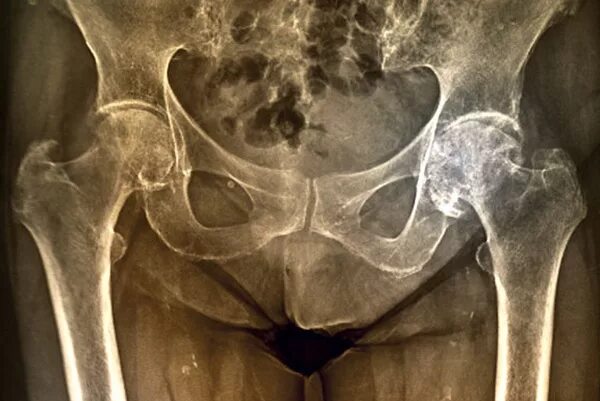

Коксартроз тазобедренного сустава 1 2